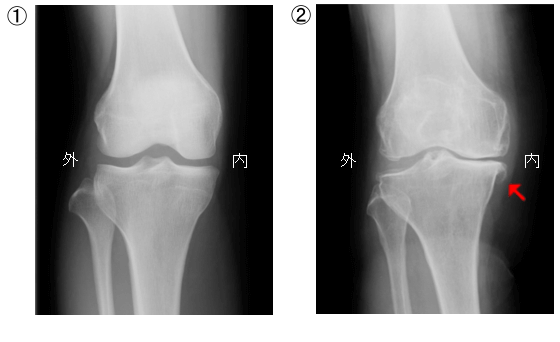

機械的なダメージや運動歴、仕事など長い期間、膝に負担がかかることで関節のクッション機能を果たしている半月板が摩耗することが原因と言われています。また骨折、靱帯や半月板損傷などの外傷、化膿性関節炎などの感染の後遺症として発症することもあります。変形には内反変形(O脚)と外反変形(X脚)がありますが内反変形の割合が多いと言われています。